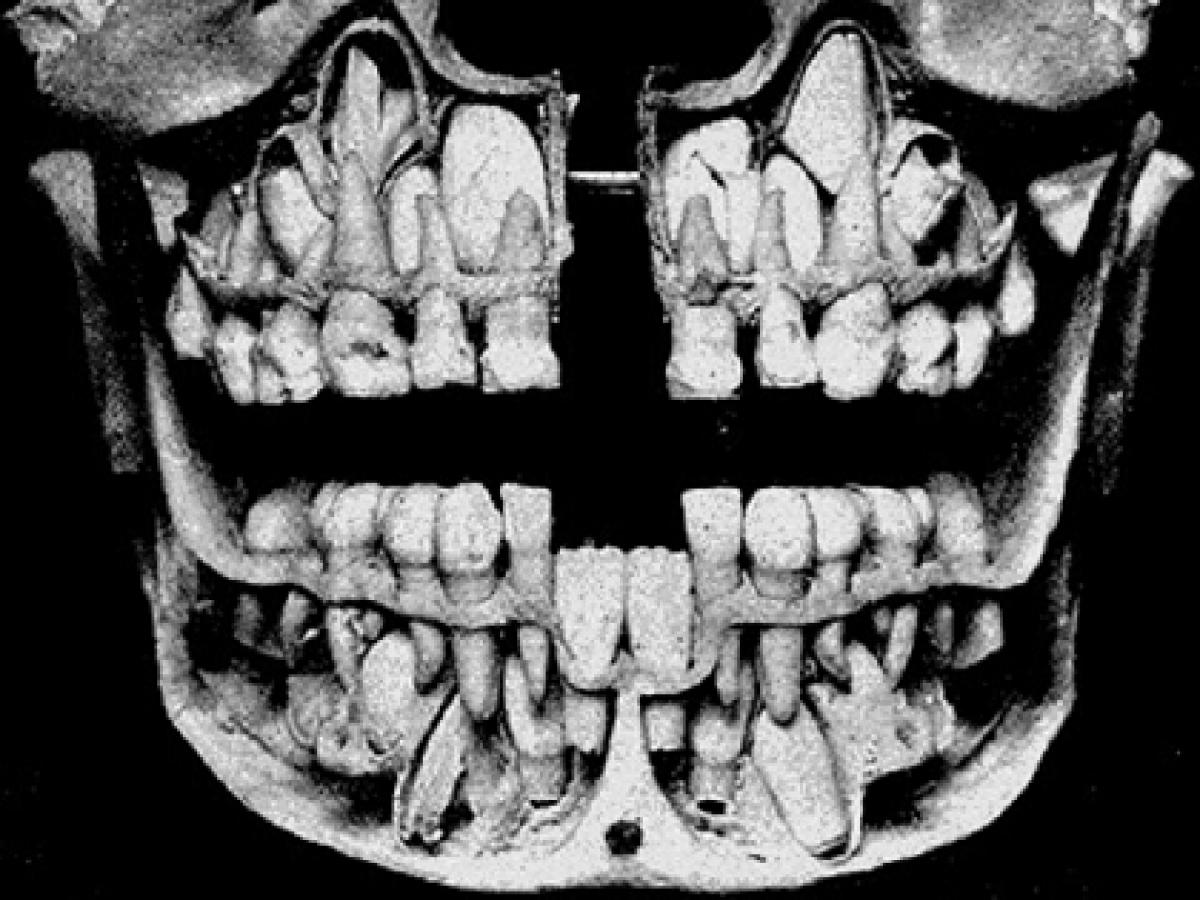

虫歯になりやすい、真っすぐ生えてこないことが多い、歯茎が腫れて痛みが出やすい――。こうしたネガティブなイメージを持たれやすい「親知らず」。

実際に歯や歯茎のトラブルを引き起こす原因となることも多いため、歯科医院で「抜いた方がいい」と言われた経験がある人も多いと思います。

そのため、ネット上では「どうせ抜かれる運命なのに、何のために生えてくるんだろう」という疑問をはじめ、「どうして生える人と生えない人がいるの?」「他の歯より、抜いた後の痛みが強いのはなぜ?」との声も多くあります。